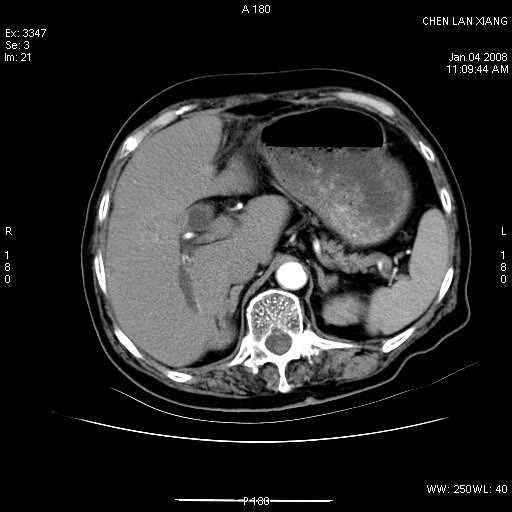

女,76岁,腹痛3-4天,b超示:肝内实性肿物,胆囊强回声,胆总管扩张.

考虑:1、胆总管下端结石伴梗阻性肝内外胆管扩张(肝左叶外侧段肝内胆管多发结石、胆管炎);

2、肿囊癌累及肝,不除外 黄色肉芽肿性胆囊炎。

1 胆总管末端结石伴肝内胆管结石,肝内外胆管扩张。2 胆囊扩大,胆囊壁不规则增厚,内见软组织密度影。考虑:慢性胆囊炎,不除外胆囊癌!

ct所见:1、 肝内胆管结石,肝内外胆管扩张。低位胆道梗阻,胆总管下端结石;2 胆囊扩大,胆囊壁不规则增厚

考虑:胆总管下端结石并肝内外胆管扩张,肝内胆管结石;

慢性胆囊炎

标题: 肝右叶病灶

胆囊癌侵犯肝右叶?

1)胆囊癌伴肝脏转移。2)胆总管下端结石、肝内胆管结石伴肝内外胆管扩张。